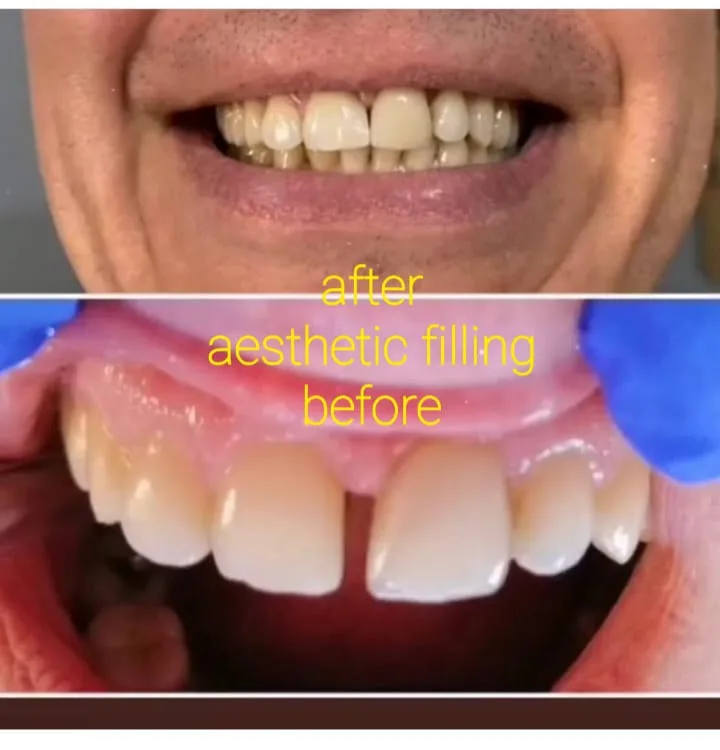

✅ طب الأسنان التجميلي: تبييض وترميم الأسنان ✅ طب الأسنان التجميلي تبييض وترميم الأسنان